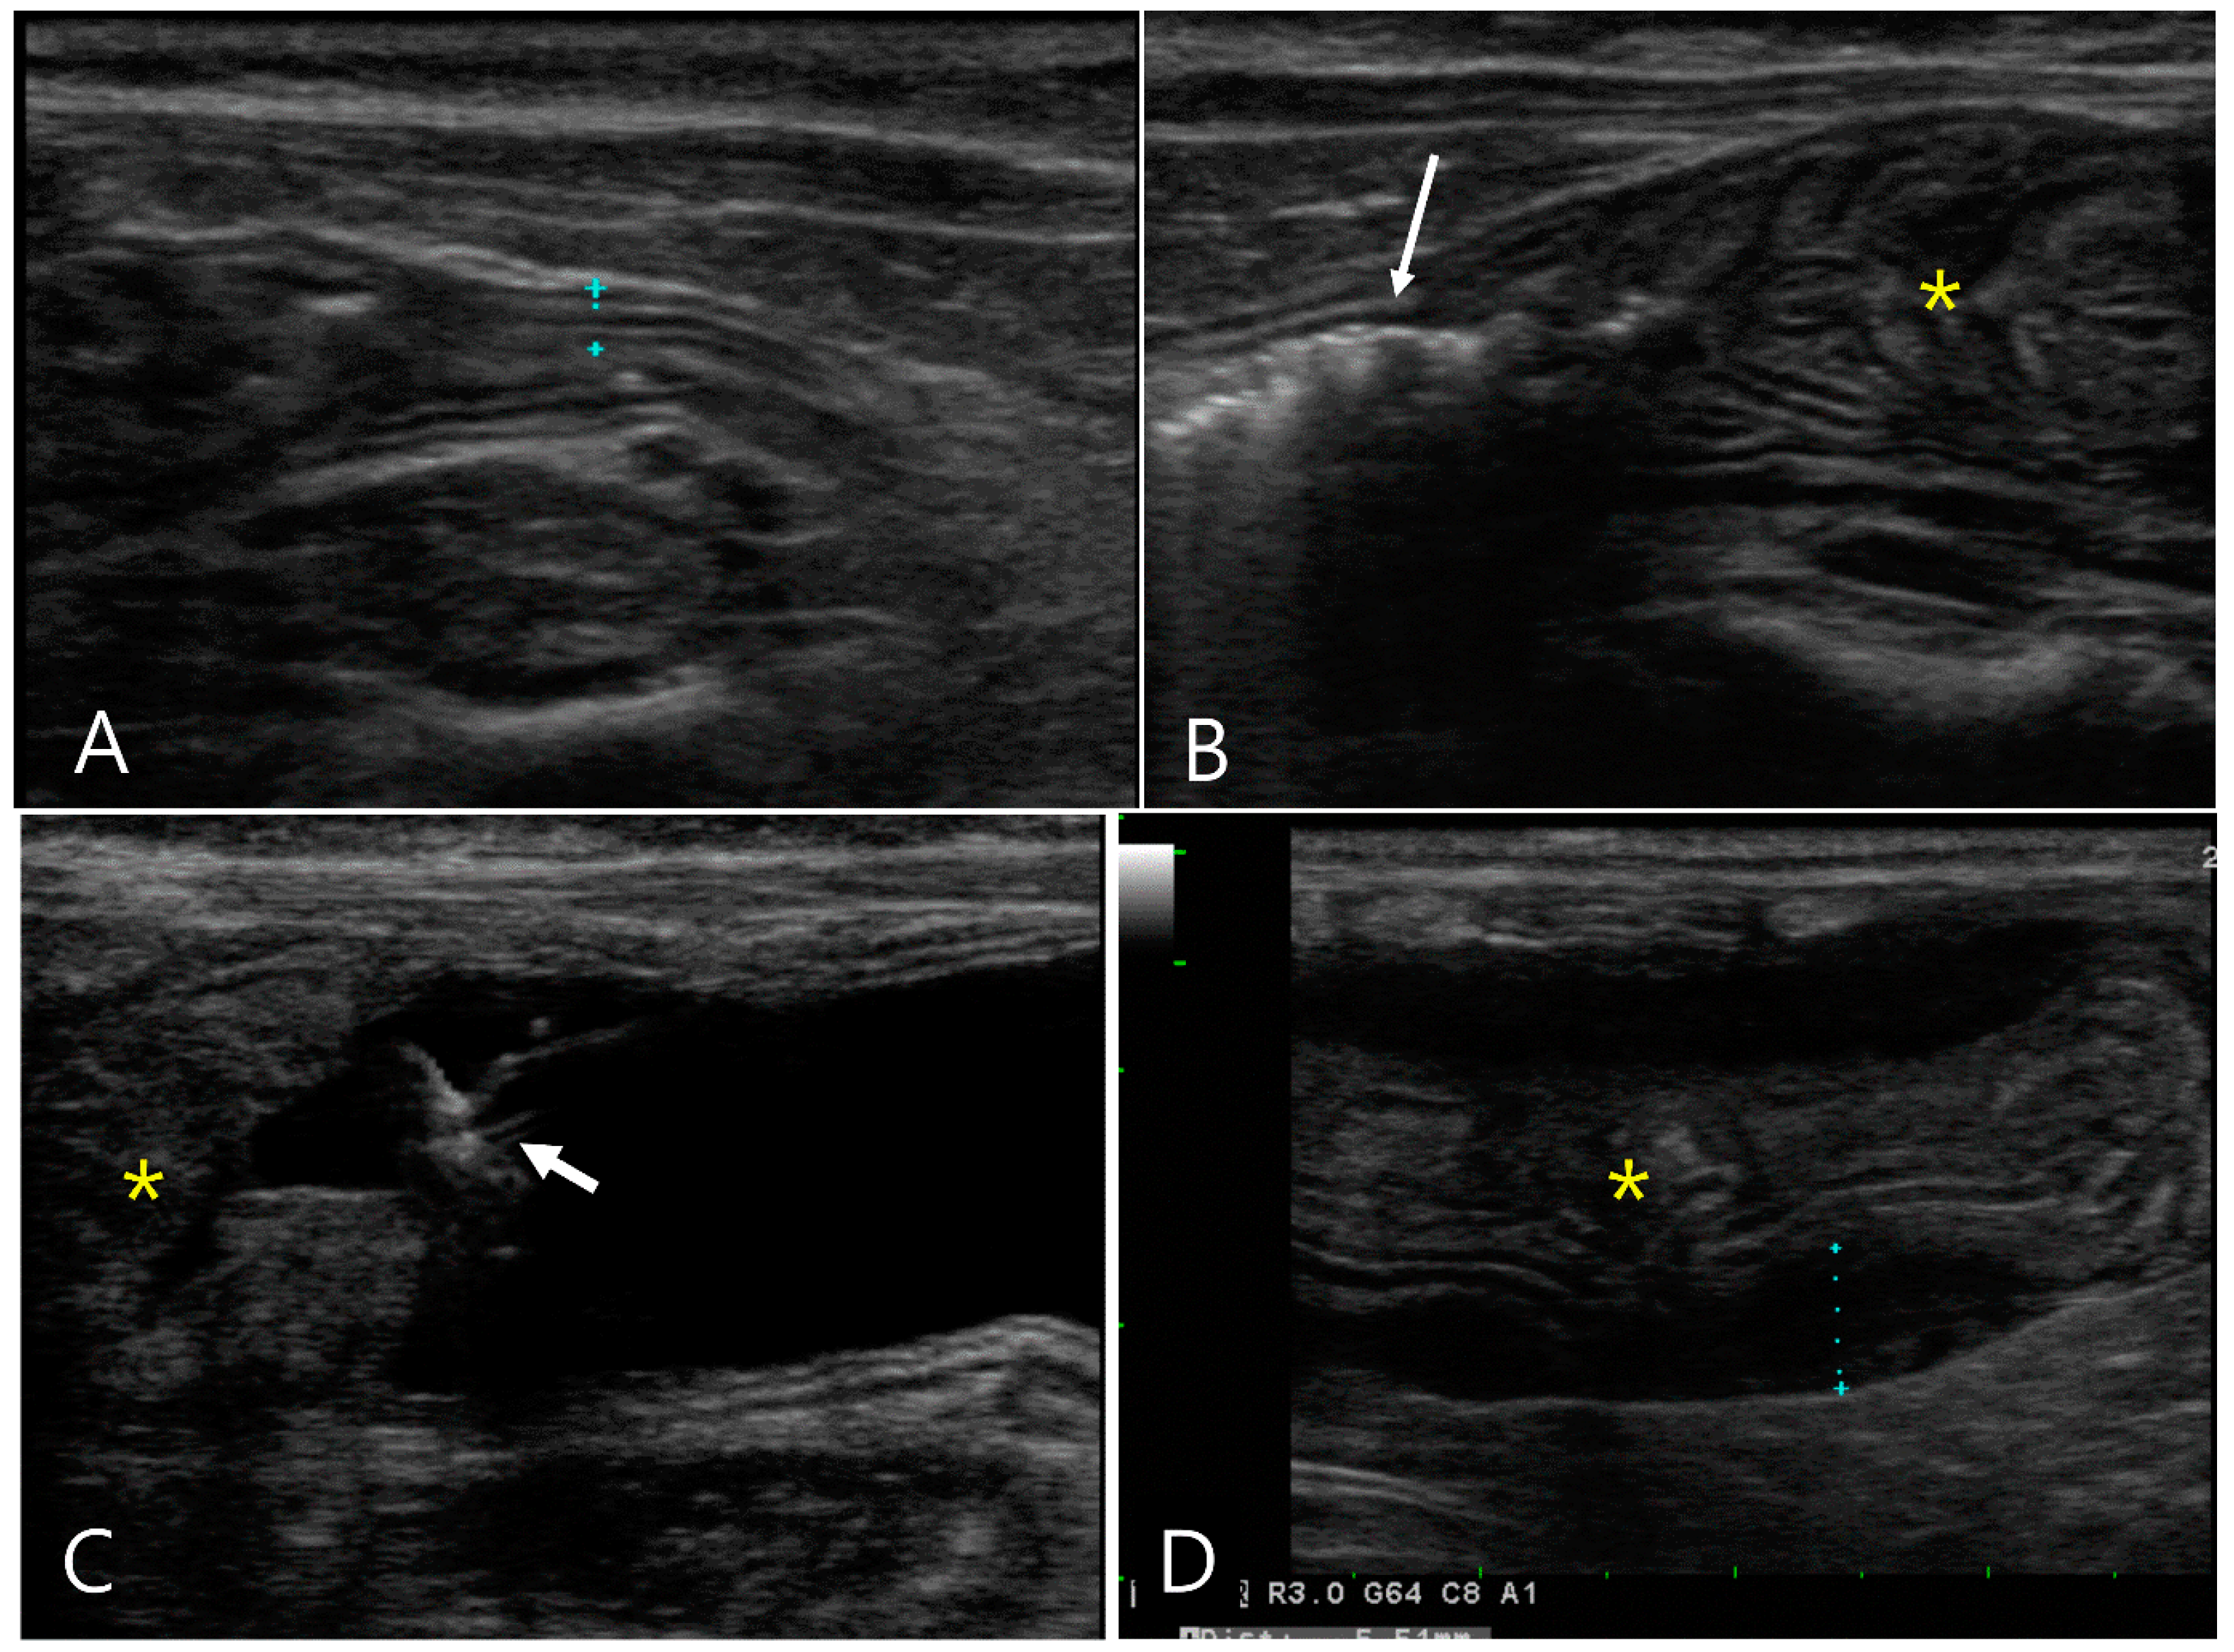

2.2. Case 2